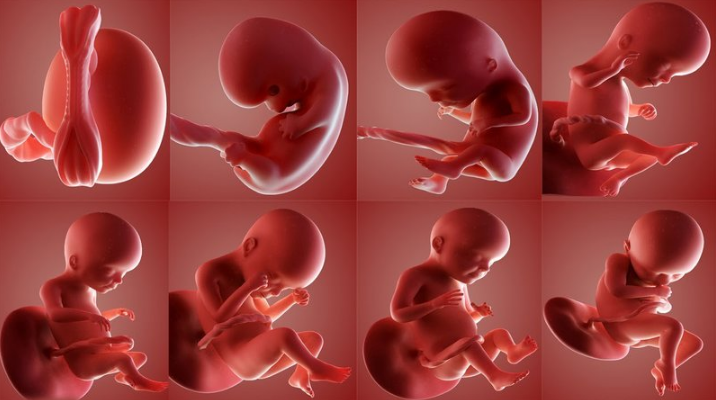

Thai nhi từ 8 đến 19 tuần tuổi: Do thai nhi luôn ở tư thế cuộn tròn trong bào thai nên rất khó đo cân nặng, kích thước của thai nhi, chỉ xác định được từ vị trí đầu đến mông. Nên , ở thời điểm này, chiều dài thai nhi còn được gọi là chiều dài đầu mông.

Thai nhi từ 20 đến 42 tuần tuổi: Chiều dài phôi thai được đo từ đầu đến gót chân. Thông qua các hình ảnh siêu âm vào giai đoạn này, bà bầu có thể quan sát thấy kích thước cũng như cân nặng của thai nhi tăng dần đều.

Đáng chú ý, từ tuần thai thứ 32 trở đi, cân nặng và kích thước của thai nhi sẽ phát triển tối đa và những đường nét cuối cùng trên cơ thể của thai nhi cũng dần được hoàn thiện.

Mẹ sẽ nhận thấy thai nhi qua các tuần thay đổi rất nhiều. Tuy thai nhi ở trong bụng mẹ khoảng 38 tuần nhưng độ dài trung bình của thai kỳ sẽ được tính là 40 tuần. Do thai kỳ được tính từ ngày đầu tiên trong chu kỳ kinh cuối cùng của mẹ, mà không phải là ngày thụ thai vào khoảng 2 tuần sau đó. Mẹ có thể tham khảo thông tin chi tiết về kích thước phôi thai cũng như sự phát triển của em bé theo tuần tuổi cụ thể như sau: